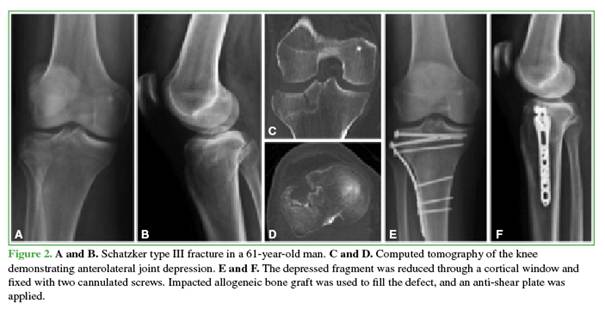

In the other procedure, the articular surface was restored with impacted bone allograft introduced through a distal window; two cannulated screws (4.5 or 6.5 mm) were then inserted, followed by additional impaction and filling with allograft to occupy the metaphyseal defect (Figure 2).